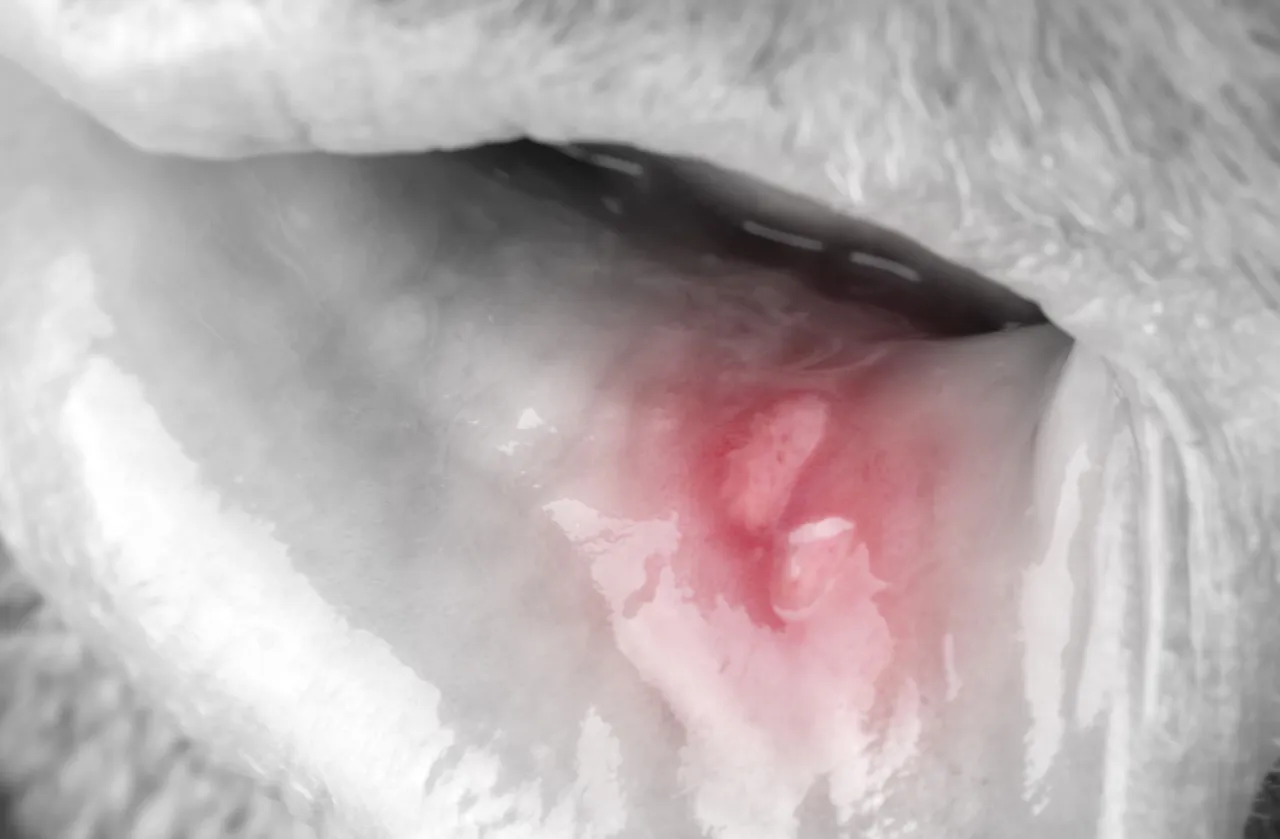

Afta to niewielkie, ale niezwykle bolesne owrzodzenie błony śluzowej jamy ustnej. Zazwyczaj przybiera postać okrągłego lub owalnego ubytku, pokrytego białym lub żółtawym nalotem, otoczonym czerwoną, zapalną obwódką. Choć jej rozmiar rzadko przekracza centymetr, ból, jaki wywołuje, potrafi znacząco utrudnić codzienne czynności, takie jak jedzenie, picie czy nawet mówienie. To sprawia, że nawet jedna, mała zmiana potrafi być prawdziwym utrapieniem.

Ważne jest, aby odróżnić aftę od innych zmian w jamie ustnej, ponieważ metody leczenia i ich charakter mogą się różnić. Afty zazwyczaj pojawiają się pojedynczo, są okrągłe lub owalne, z charakterystycznym białym nalotem i czerwoną obwódką. Lokalizują się na błonie śluzowej policzków, warg, języka czy dna jamy ustnej. Co istotne, afty nie są zakaźne. Pleśniawki, czyli grzybica jamy ustnej, objawiają się zazwyczaj jako biały, serowaty nalot, który można zetrzeć, odsłaniając zaczerwienioną błonę śluzową; często towarzyszy im pieczenie. Opryszczka wargowa, wywoływana przez wirusa HSV, zwykle pojawia się na zewnętrznej części wargi jako skupisko pęcherzyków, które pękają i tworzą strupki; jest wysoce zakaźna.